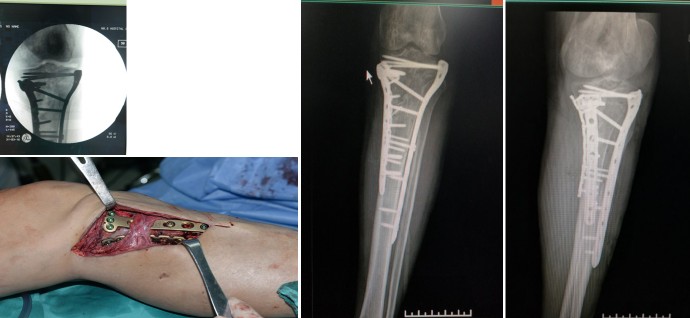

复合组织缺损

患者 男,68岁。因左小腿外伤后骨外露伴皮肤缺损20天入院。左小腿外支架固定中,左胫骨大段骨质外露,左小腿大面积皮肤软组织缺。入院后行清创死骨去除VSD术。术后1周行左胫骨骨迁移+左背阔肌游离移植术+取皮植皮术(图1-5)。术后14天开始胫骨骨迁移,创面一期愈合。术后1年随访,皮瓣外形良好(图6)。术后20月,迁移骨成骨良好,骨端愈合,拆除外固定支架(7)。